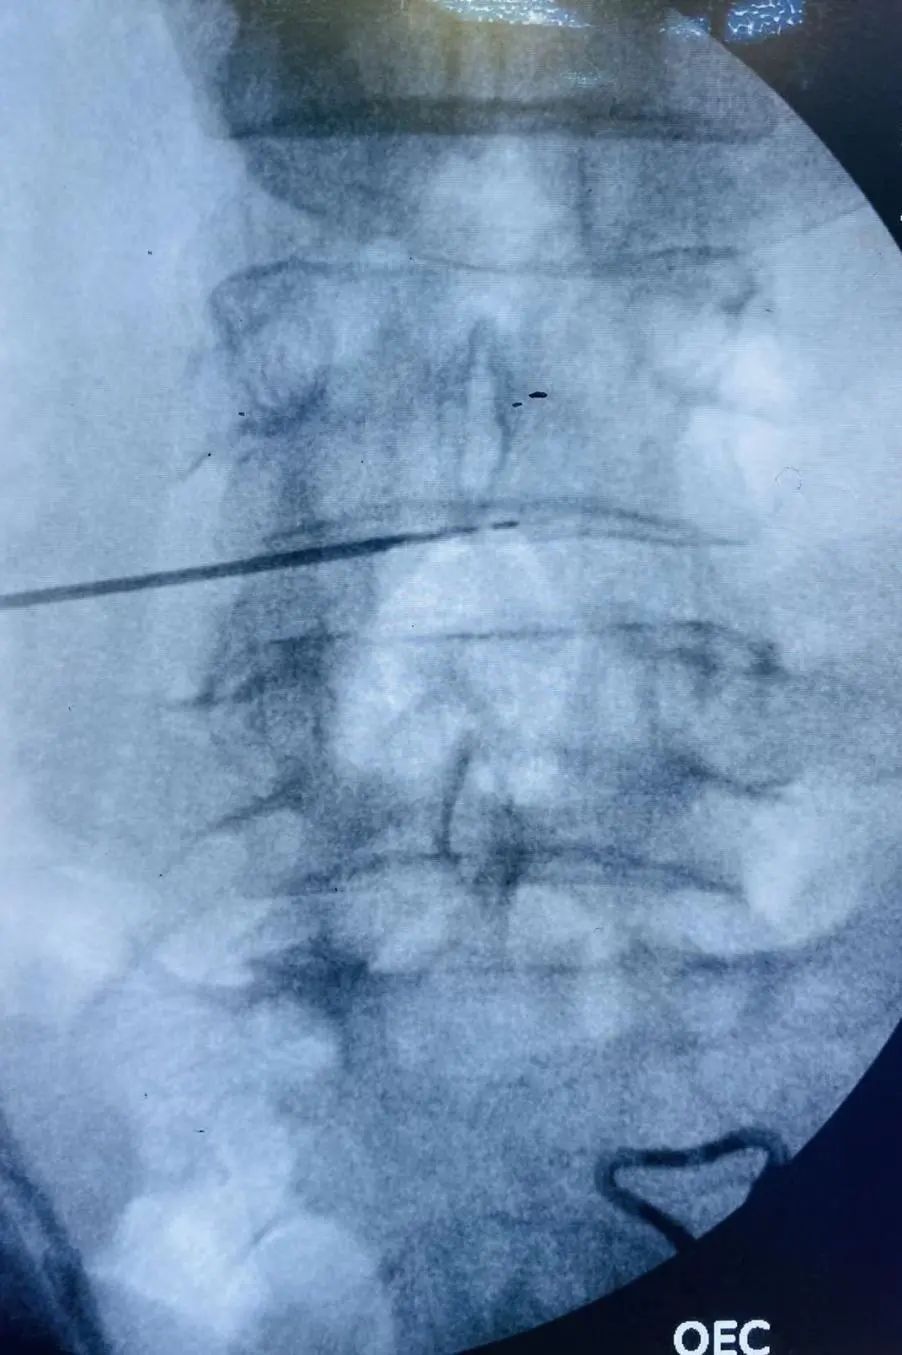

于6月9日在手术麻醉科配合下,脊柱外科管廷进主任医师、孙鹏副主任医师、苏凯主治医师在局部麻醉下为患者实施L4/5椎间盘低温等离子射频消融、椎间盘汽化微创手术,手术顺利,术后患者腰腿痛不适症状即刻缓解。

低温等离子射频消融术的原理是通过等离子刀将射频能量作用于椎间盘内部,汽化消融部分椎间盘髓核组织,然后再利用精确的热皱缩技术将刀头接触到的髓核组织加温至约70度,使髓核体积缩小,降低椎间盘内压力,从而缓解椎间盘突出对神经根的压迫而达到治疗的目的。